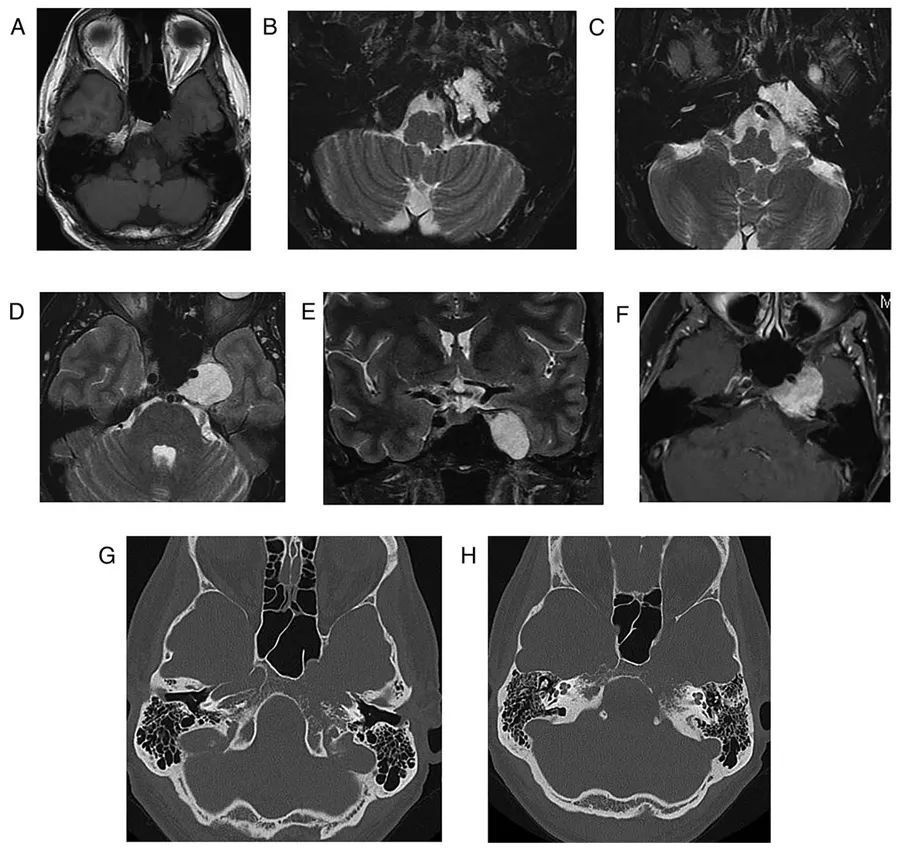

图2  肺部原发肿瘤转移。左侧桥小脑区可见转移灶,当桥小脑区结构不清时,有时很难区别是轴内病变还是轴外病变。这种不均匀的强化提示转移瘤,小脑无水肿则提示轴外病变

图3  结核瘤。左侧小脑表面可见一环形强化的结核瘤,膨胀进入桥小脑角区,并呈现出类似于轴外病变的外观,不过由于存在小脑水肿,该病灶更可能源于轴内。此外,右侧外侧裂可见脑膜强化,即脑膜炎的证据

图4  巨大椎基底动脉连接处动脉瘤。患者表现为延髓症状,影像学显示左侧桥小脑角区不规则占位性病变,并呈流空信号,第四脑室受压变形,通过血管造影最终证实了巨大动脉瘤的诊断

图5  右侧桥小脑角区脑膜瘤。可见类圆形病灶压迫右三叉神经和脑桥,增强扫描可见显著均匀强化,强化的硬脑膜尾沿着颞骨岩部向下延伸

图6  左侧桥小脑角区表皮样囊肿。病灶呈T1低信号、T2高信号,DWI上弥散受限,延伸至Meckel氏腔,左侧小脑中脚和第四脑室受压,三叉神经、面神经、听神经也被压缩

图7  蛛网膜囊肿。可见右侧桥小脑角区呈脑脊液信号的不规则肿物,右侧小脑半球受压变形

图8  双侧桥小脑角区脂肪瘤。T1WI上呈现高信号,压脂像上则无信号。如果只根据增强扫描的图像(E和F),很容易将脂肪瘤误认为前庭神经鞘瘤或脑膜瘤